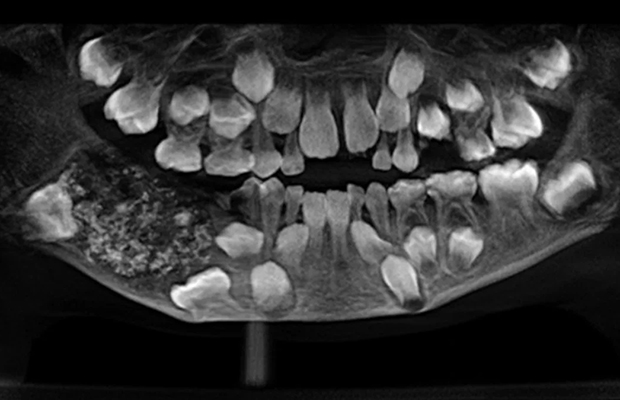

Las radiografías y tomografías computerizadas revelaron la presencia de una masa de aproximadamente 200 gramos alojada en el interior de la mandíbula. El Dr. Senthilnathan, responsable del Departamento de Cirugía Oral y Maxilofacial, identificó la anomalía como un “odontoma compuesto”, una variante benigna de tumor directamente relacionada con el desarrollo dental.

“La especie de tumor que detectamos impidió el crecimiento permanente de los molares en el niño en el lado afectado”, explicó el cirujano tras completar la operación. Las imágenes médicas mostraban numerosos dientes rudimentarios agrupados en un tejido con forma de bolsa, una presentación clínica poco frecuente en la literatura especializada.

La magnitud del descubrimiento sorprendió incluso a los médicos más experimentados. Según informó Science Alert, la bolsa contenía 526 pequeños dientes de dimensiones variables, desde apenas 0,1 milímetros hasta 15 milímetros de longitud. El proceso de clasificación y contabilización de cada pieza dental requirió cinco horas adicionales de trabajo meticuloso en el laboratorio.

La Dra. Pratibha Ramani, directora del Departamento de Patología Oral y Maxilofacial, destacó que todos los dientes extraídos presentaban las estructuras características de las piezas dentales normales: corona, raíz y recubrimiento de esmalte. “Incluso la pieza más pequeña tenía las características de un diente tradicional”, subrayó la especialista, quien enfatizó la ausencia de precedentes con tal número de dientes en los registros médicos mundiales.